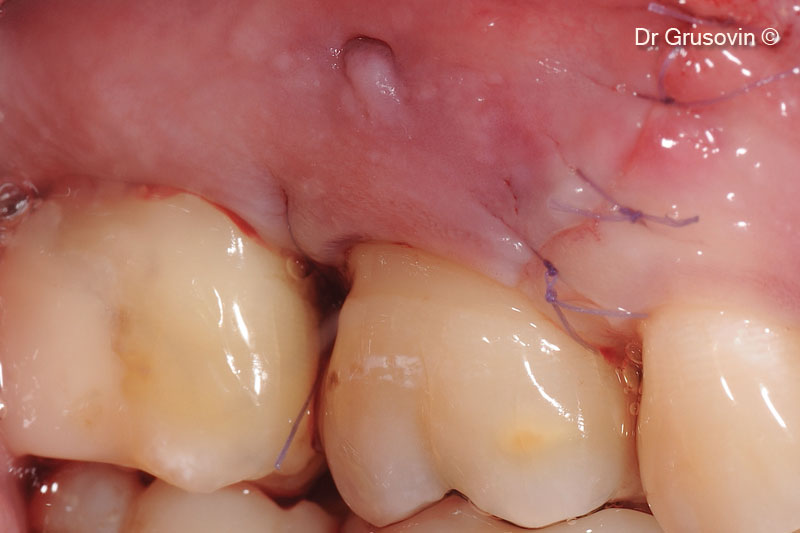

Quan sát lâm sàng trong quá trình phẫu thuật: tổn thương vùng tiền đình và nhánh chẻ III xa.

OsteoBiol® Gen-Os® được cấy ghép vào tiền đình

OsteoBiol® Gen-Os® được cấy ghép vào tiền đình.

Khâu đóng vạt bảo tồn nhú